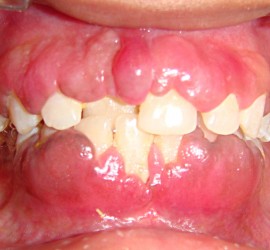

Аномалии строения и пороки развития зубов Пороки тканей зуба многообразны, они могут проявляться изолированно и сочетаться с аномалиями строения и пороками развития органов и систем всего детского организма, в том числе челюстно-лицевой области. Ткани зуба имеют эктодермальное (эмаль) и мезодермальное (дентин, пульпа, цемент) происхождение. В связи с этим пороки эмали […]